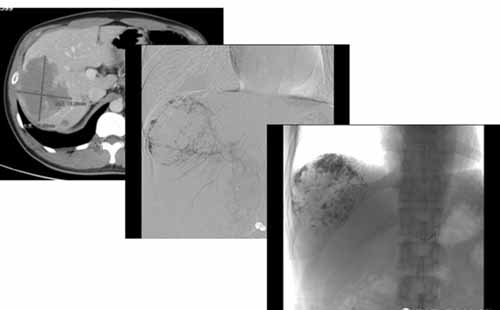

肝血管瘤的介入栓塞硬化治療,即經導管肝動脈栓塞術( TAE) ,手術方法為:介入醫師采用Selding er 技術, 經股動脈穿刺,用導管或微導管在導絲指引下, 選擇或超選擇造影, 明確肝血管瘤的大小、部位、多少。然后將導管頭端插入血管瘤的供血動脈( 靶血管) , 選擇合適的栓塞材料,在監視下緩慢栓塞。根據患者的狀況, 血管瘤栓塞滿意后, 再用明膠海綿條將血管瘤的供血動脈閉塞。栓塞完畢行肝動脈造影以評定栓塞效果。巨大型的血管瘤可分期、分次栓塞。

我們來看一個典型病例:

(手術過程:通過DSA下動脈造影,找到供血動脈,注入栓塞劑進行栓塞。)